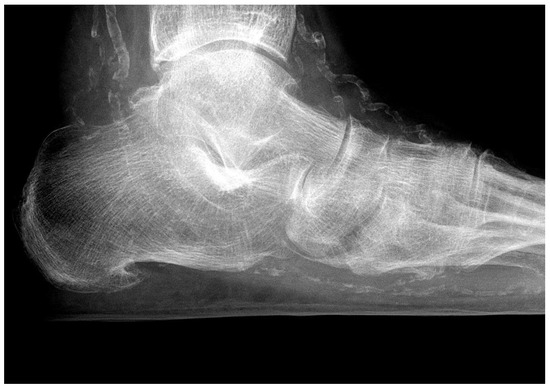

4.1. Skeletal Problems

| skeletal changes | rare | frequent (Charcot foot) |